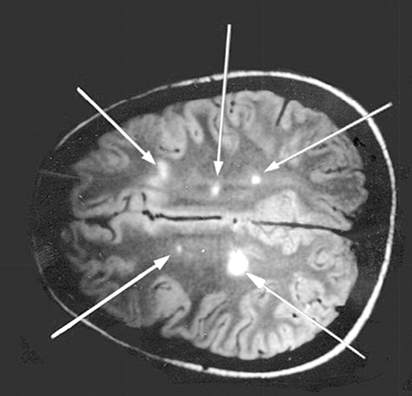

What is the main Diagnostic Criteria for Multiple Sclerosis?

McDonald Criteria, which require evidence of:

1. Dissemination in space (DIS)

Lesions in different CNS regions

“Two separate attacks”

Demonstrated via MRI (90% positive)

2. Dissemination in time (DIT)

Evidence that lesions occurred at different points in time

“Two separate lesions”